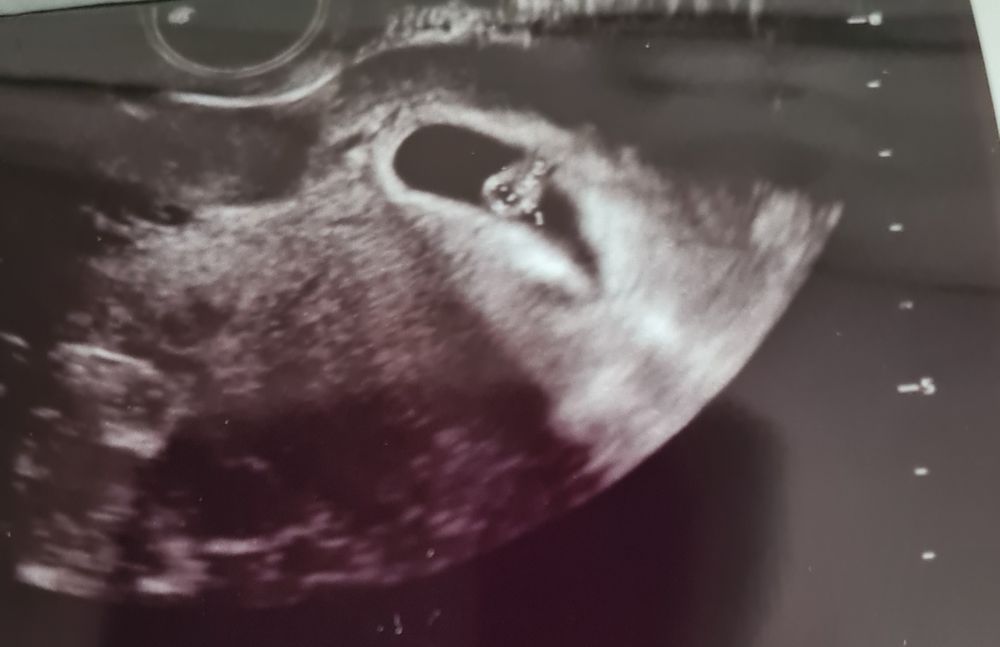

Yolochka, 6недель и 5 дней тут мне узист первый раз сказал "девчонка там!" Но мне не верится конечно. Изображение

29.09.2022

Анна, нашла я уже ваши ранние узи по постам) тоже скажу, что по методу Рамзи - девочка, если узи вагинально делали. Э прикреплён справа. Если б слева - мальчик. Можете сравнить, если остались узи с прошлых Б, только срок до 8 нед должен быть.